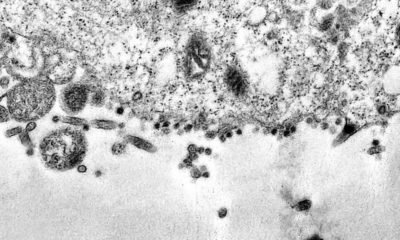

Pesquisa do Centro de Estudos do Genoma Humano e Células-Tronco, do Instituto de Biologia da Universidade de São Paulo (IB-USP), sugere que os homens podem ser...

Um estudo feito por pesquisadores da Universidade Médica de Chongqing, na China, mostrou que a CoronaVac, vacina da farmacêutica chinesa Sinovac contra a covid-19, fabricada no...

A Agência Nacional de Vigilância Sanitária (Anvisa) autorizou novo estudo clínico para o desenvolvimento de uma vacina contra a covid-19. A pesquisa será realizada em fase...